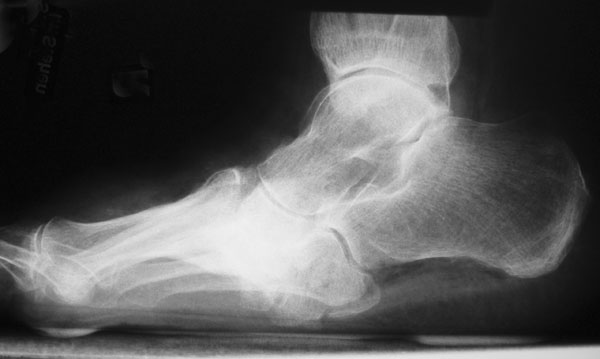

Der Knickfuß geht in der Regel mit einer abgeflachten Längswölbung (Senkfuß) und im fortgeschrittenen Stadium mit einer Aufhebung der Längswölbung (Plattfuß = Pes planus) (Abb. 2a) einher. Man spricht dann von einem sogenannten Knick-Plattfuß (Pes plano-valgus) 8. Beim DFS gilt es einen vorbestehenden Plattfuß, der evtl. noch flexibel ist, von einem strukturellen, kontrakten Plattfuß bei Einbruch des Fußlängsgewölbes im Rahmen einer Osteoarthropathie zu unterscheiden. Mit dem Jack‘s-Test lässt sich prüfen, ob der sog. Windlass-Mechanismus (Windenmechanismus) intakt ist (Mann 2013).

Ein Spitzfuß (Pes equinus) kann sowohl durch eine Verkürzung von Achillessehne, M. gastrocnemius und M. soleus, aber auch durch ein mechanisches Extensionshindernis im oberen Sprunggelenk bedingt sein. Folge der Spitzfußstellung ist eine deutliche Druckumverteilung mit Mehrbelastung des Vorfußes. Typisches Merkmal des Hohlfußes (Pes cavus) (Abb. 2b), welcher oft mit einer Rückfußvarusstellung kombiniert ist, ist ein pathologisch überhöhtes Fußlängsgewölbe. Er ist meist Folge neuro-muskulärer Grunderkrankungen.

Der Schaukelfuß oder Tintenlöscherfuß (Abb. 2c und d) ist beim Patienten mit DFS meist alleinige Folge einer Osteoarthropathie mit komplettem Einbruch des Fußlängsgewölbes durch eine Gelenkdestruktion im Bereich zwischen Lisfranc- und Chopartgelenk.

Eine Varus- oder Valgusdeviation des Vorfußes wird als Pes adductus (Sichelfuß) oder Pes abductus bezeichnet. Der häufigere Pes abductus ist bei fortgeschrittenem Plattfuß auf eine mediale Subluxation des Taluskopfes im Talonaviculargelenk zurückzuführen. Häufig findet sich eine Vorfußverbreiterung (Spreizfuß, Pes metatarsus) (Abb. 2e) mit sekundären Deformitäten der Zehen (Hallux valgus) und Zeichen eines chronischen Tiefertretens des Metatarsale 2-4 (Metatarsalgie, Fehlbeschwielung).